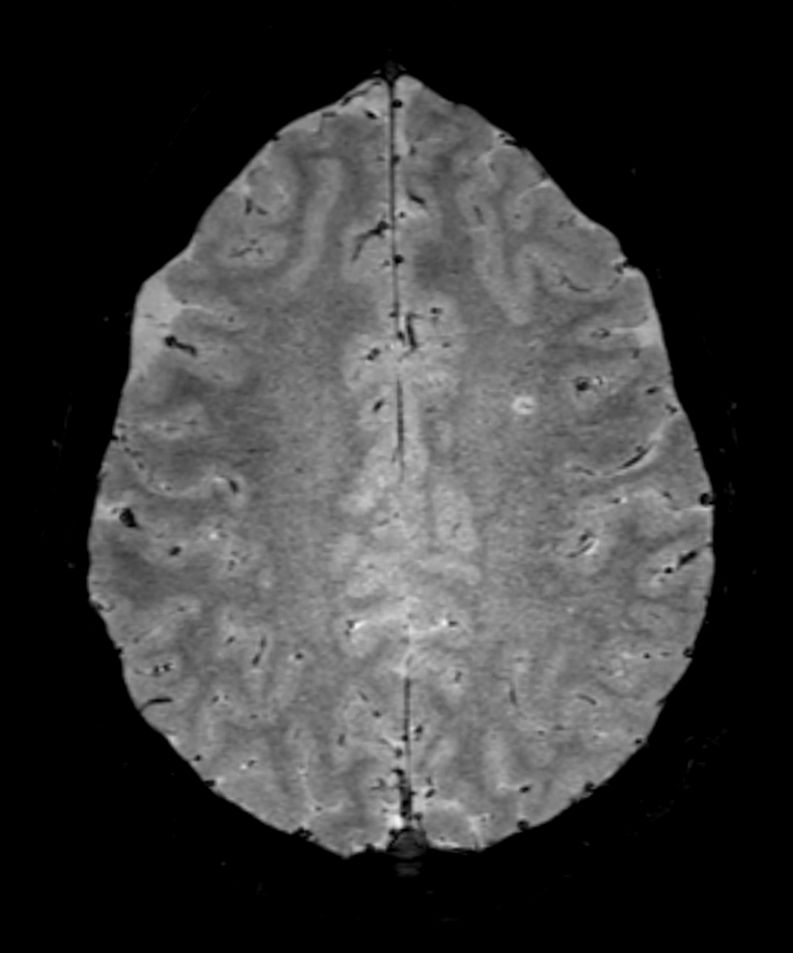

SWI sequence has a high sensitivity to enhance contrast for deoxygenated (venous) blood or calcium deposits. This may help, when used in combination with other clinical information, in the diagnosis of various neurological pathologies. 3D imaging lets you acquire high resolution data in multiple directions in one scan. Isotropic voxel size enables reformats in any plane without loss of resolution. FLAIR* requires offline post processing combining the contrast of 3D FLAIR and 3D SWI EPI into a single image. This enables the visualization of Central Vein Sign, mapping subcortical veins onto 3D FLAIR contrast images.